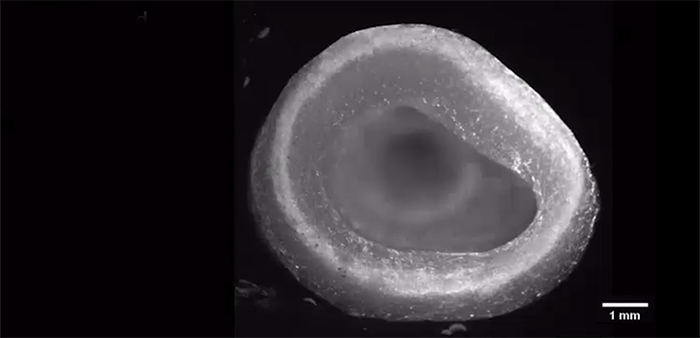

Forscher der Carnegie Mellon University haben eine Methode entwickelt, die Organzucht im Labor zu verbessern. Wie auf der Website der Universität geschrieben wird, können menschliche Organteile und Organe damit in feinsten Mikrostrukturen erzeugt werden. Eine linke Herzkammer aus Kollagen und Herzmuskelzellen war der erste Test für diese Technik. Die Kammer begann nach wenigen Tagen von selbst zu schlagen. Details dazu wurden im Fachmagazin „Science“ veröffentlicht.

Die Mikrostrukturen menschlicher Gewebe und Organe lassen sich nicht so leicht nachbilden. Doch sie entscheidend, wenn es um die Funktion der Organe geht. Es ist schwierig, das zu Beginn der Prozedur noch flüssige Kollagen für das Grundgerüst in Form zu bringen. Die neue Methode von Andrew Hudson von der Carnegie Mellon University in Pittsburgh und seinem Team erlaubt feinste Mikrostrukturen aus Kollagen. So können die Forscher nun Organgerüste aus Kollagenfasern von nur 25 Mikrometern Dicke drucken. Zellbesetzte Organteile wurden mit der FRESH (Freeform Reversible Embedding of Suspended Hydrogels) getauften Methode angefertigt.

Das Bad in zähem Hydrogel beim 3D-Druck sorgt für winzige Kollagenstrukturen, die nicht aus der Form geraten und Hohlräume und Poren gedruckt werden können. Durch die Verkleinerung der Moleküle auf 25 Mikrometer nimmt die Auflösung der Teile zu. Ist der Druck fertig, härtet die Kollagenlösung aus. Das Organmodell wird erwärmt, wodurch das Hydrogel wegschmilzt. Die FRESH-Methode sorgt dafür, dass auch komplette Organteile, dessen Zellen, biologische Materialien und feinste Verästelungen von Gefäßen möglich sind.